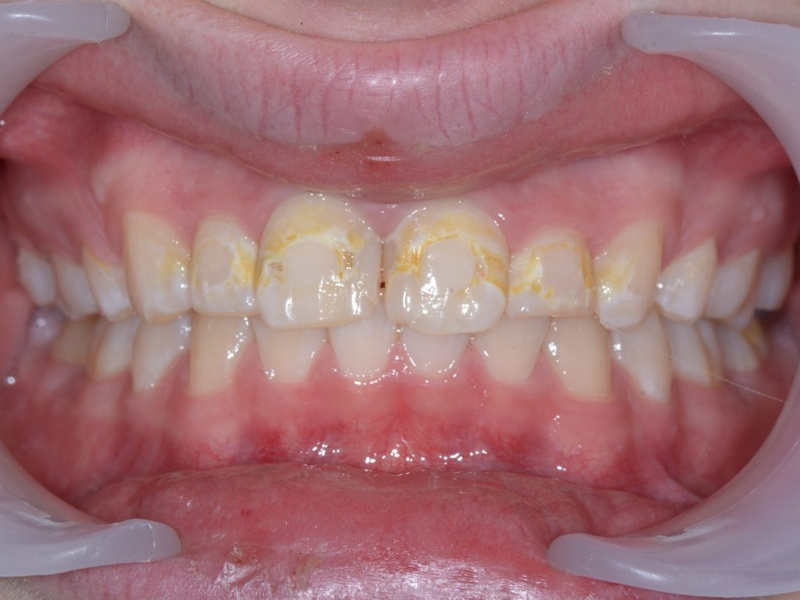

Grav initialkaries